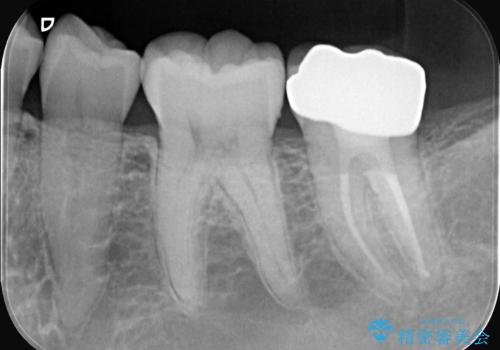

- 昨日からのズキズキとした激しい痛みを主訴にご来院されました。レントゲンおよび歯髄診察の結果、不可逆性の歯髄炎(歯の神経の重度の炎症)と診断。歯を残すことを第一に、まず痛みの原因である神経を取り除く根管治療を提案しました。また、虫歯が歯肉の下まで深く進行していたため、根管治療後に歯周外科処置を行い、最終的に精密なセラミッククラウンで修復する、総合的な治療計画を立案しました。

治療はまず、根管治療から始め、感染した神経を徹底的に除去することで、痛みをすぐに解消しました。再発を防ぐため、ラバーダムや顕微鏡を使って、根管内を丁寧に、そして精密に処置しました。次に、深い部分の虫歯を確実に治療するため、歯周外科処置を行い、治療しやすい環境を整えました。最後に、機能と見た目に優れたセラミッククラウンを作製・装着。根管治療から外科処置、審美修復までを一貫して行うことで、再発リスクの低い、長期的に安定して使える奥歯を取り戻していただけました。